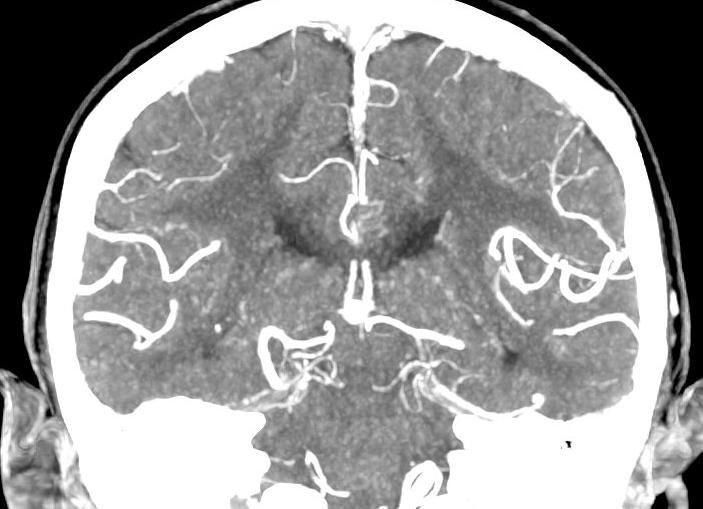

Ситуации, при которых требуется делать томографию головы, возникают довольно часто: эта процедура незаменима, когда нужно обследовать головной мозг, сосуды головы и шеи, а также костную ткань.